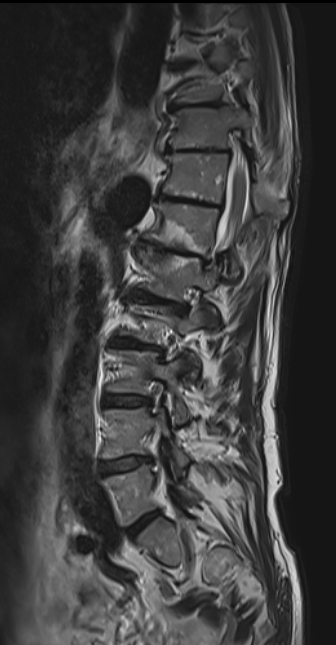

Nou wist ik al langer dat mijn rug niet al te best is. In 2008 heb ik al eens een crisis met m’n rug gehad. De orthopedist Dr. Hardt wist mij toen te zeggen ‘meneer Mol, u hebt drie hernia’s, ik ga daar niets aan doen, u kunt daar heel oud mee worden’.

Een creatief geregelde MR in Brugge. Bezoek aan de fysische geneesheer: ‘Meneer, ‘mooi oud worden’ is een fabeltje’. En veel kine. Allemaal erg hoopvol.

En in augustus een voet die opeens blijft hangen. Opnieuw een MR en een bezoek aan de neurochirurg. Die gaat opereren, begin september. De avond voor de operatie, na een definitieve MR besluit ze, ‘weet je wat, ik ga het niet doen, ik heb geen idee wat er bij jouw aan de hand is. en ik zeg altijd, met een rug heb je een kans. Ik weet bij jouw waar ik aan begin, maar niet waar ik eindig. Dat is geen goed plan’. Terecht natuurlijk, maar ik blijf zitten met een voet die het niet doet.

Twee weken later gaat het helemaal mis met mijn rug. Ik heb nog nooit zoveel pijn gehad. En nu gaat dezelfde chirurg mij wel opereren.